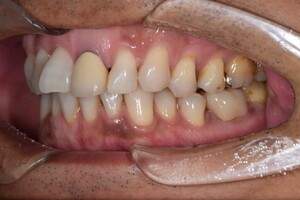

症例1

治療前

治療後

治療内容

口腔内の銀歯を全てセラミックにしたいというご希望でした。親知らずは抜歯しています。笑ったときや自然なスマイルをしたときも銀歯が見えなくなり自然になりました。

治療期間 約2ヶ月

治療費 合計:935,000円 (内訳)

オールセラミック:110,000円×5本

セラミックインレー:55,000円×7本

治療のリスク・副作用 銀歯の下で虫歯が大きくなっていたら歯の中の神経をとらないといけないことがあります。また、被せ物を外すと、ご自身の歯が少ない場合は別途はを残すための処置が必要になることがあります。